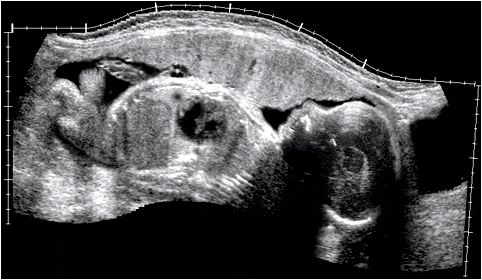

Ecotomografía de un feto de término que muestra en un corte longitudinal la proporción entre las distintas regiones corporales. Observe en el tronco lo reducido del torax en comparación con la cavidad abdominal.